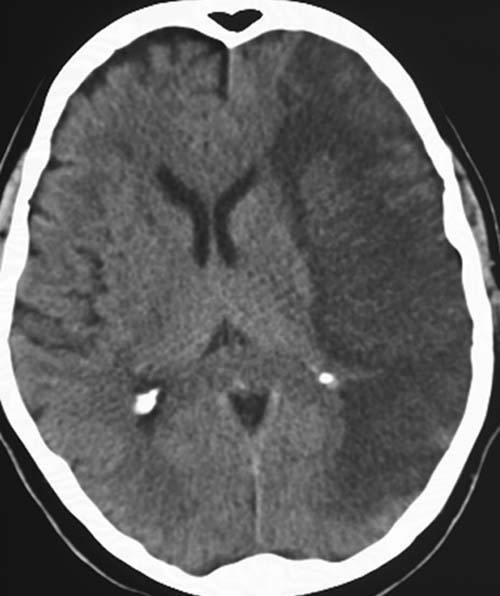

CCT nativ (ohne Kontrastmittel).

Hypodense

Darstellung des Mediastromgebietes links mit Ausnahme der Stammganglien.

Fehlende

Mark-Rinden-Differenzierbarkeit der

Rindenmarkgrenze links.

Fehlende Abgrenzbarkeit der äußeren Liquorräume.

Subakuter

raumfordernd wirkender Mediainfarkt links (48-96h). Da die Stammganglien

intakt sind, liegt der Mediaverschluss distal nach Abgang der lenticulostriären Äste.